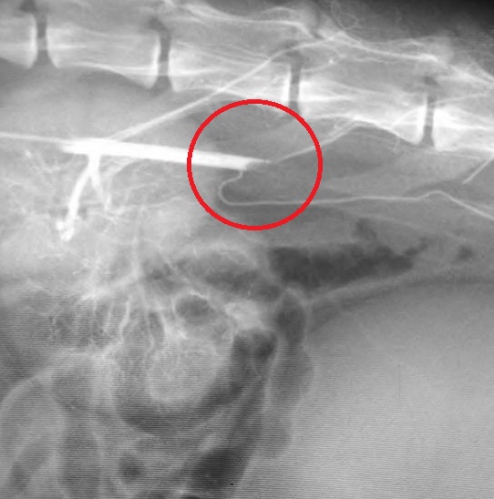

次の写真は、上写真の赤矢印先の塞栓部位の拡大像です。